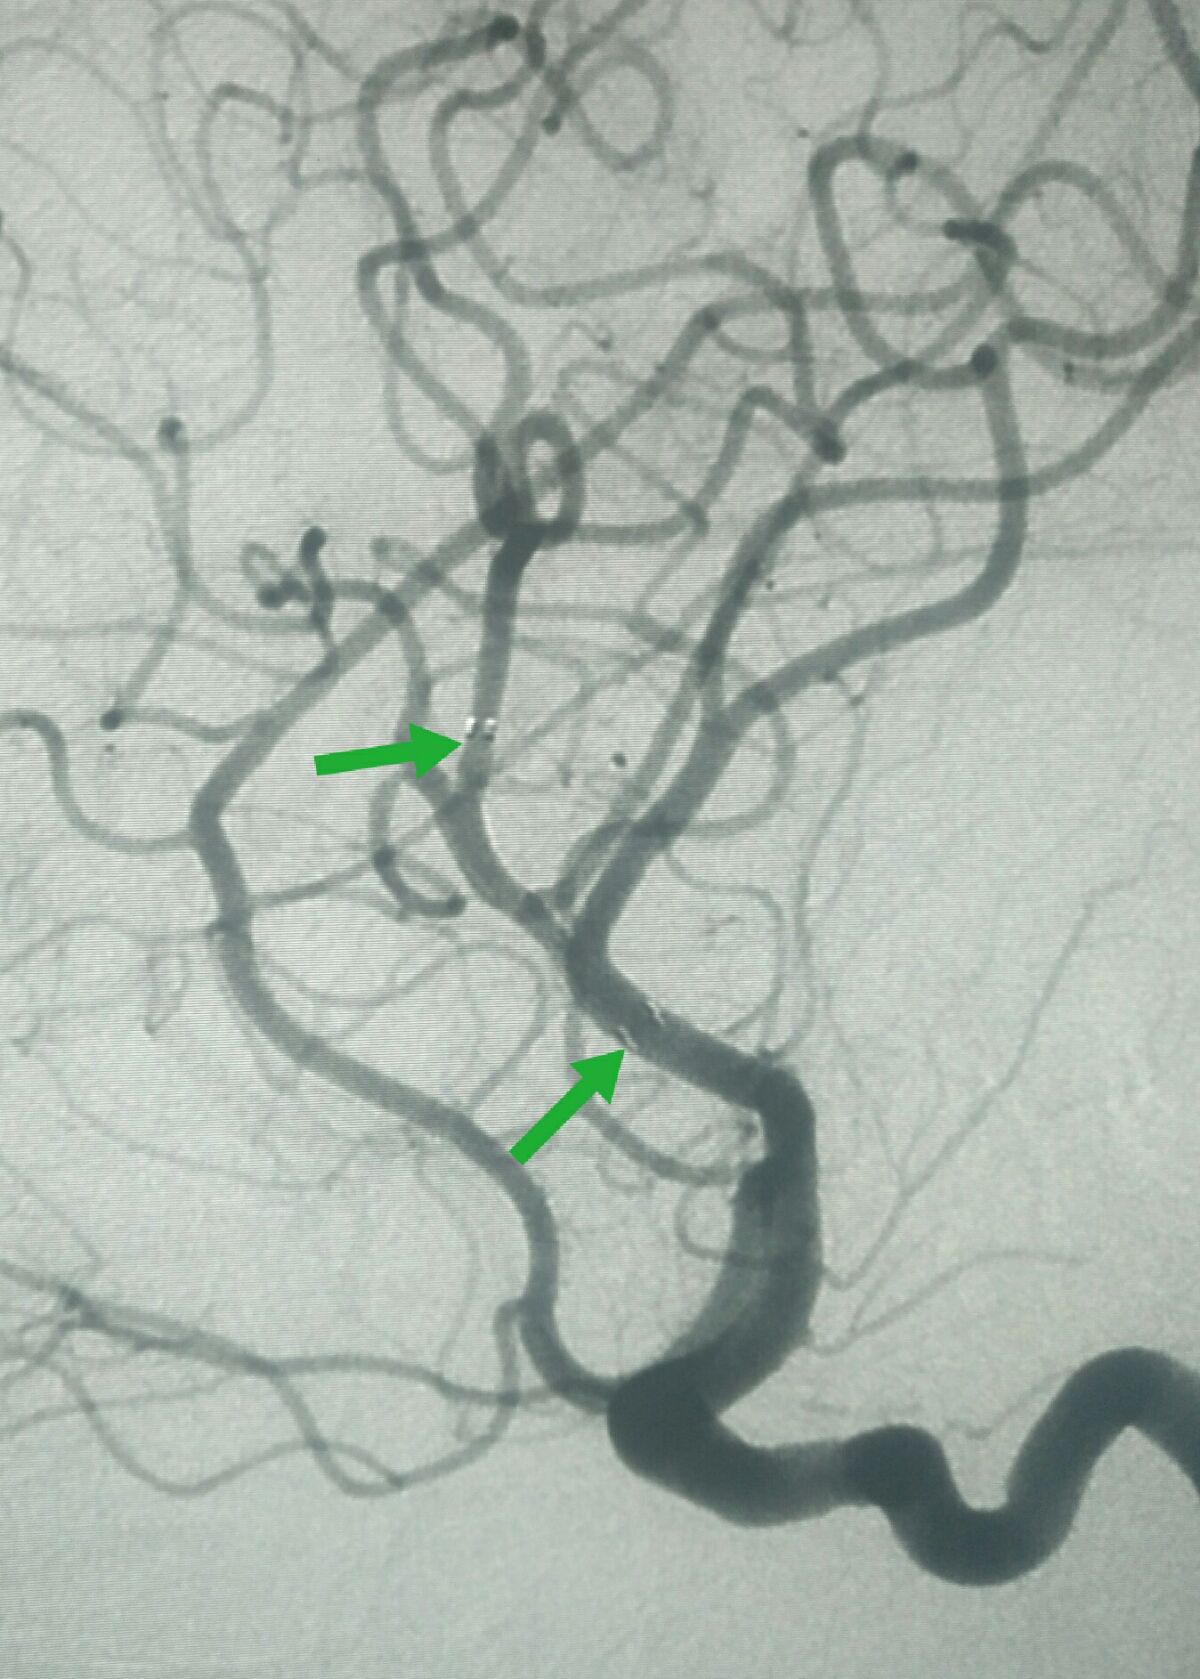

工作位造影显示支架展开充分,血管形态良好

正位造影显示血管形态良好,远端血流明显改善